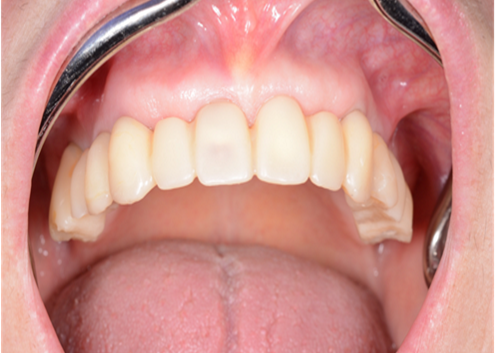

Clinical case: AFull transition from natural teeth to all-on-6 bridges

with AnyRidge implants

- Courtesy of Dr. Rabih Abi Nader, UAE -

Keywords

Full-mouth rehabilitation, minimal layering, Zirconia, all-on-6, life changing result, edentulous ,Dr. Rabih Abi Nader, AnyRidge

Products:

AnyRidge implant system